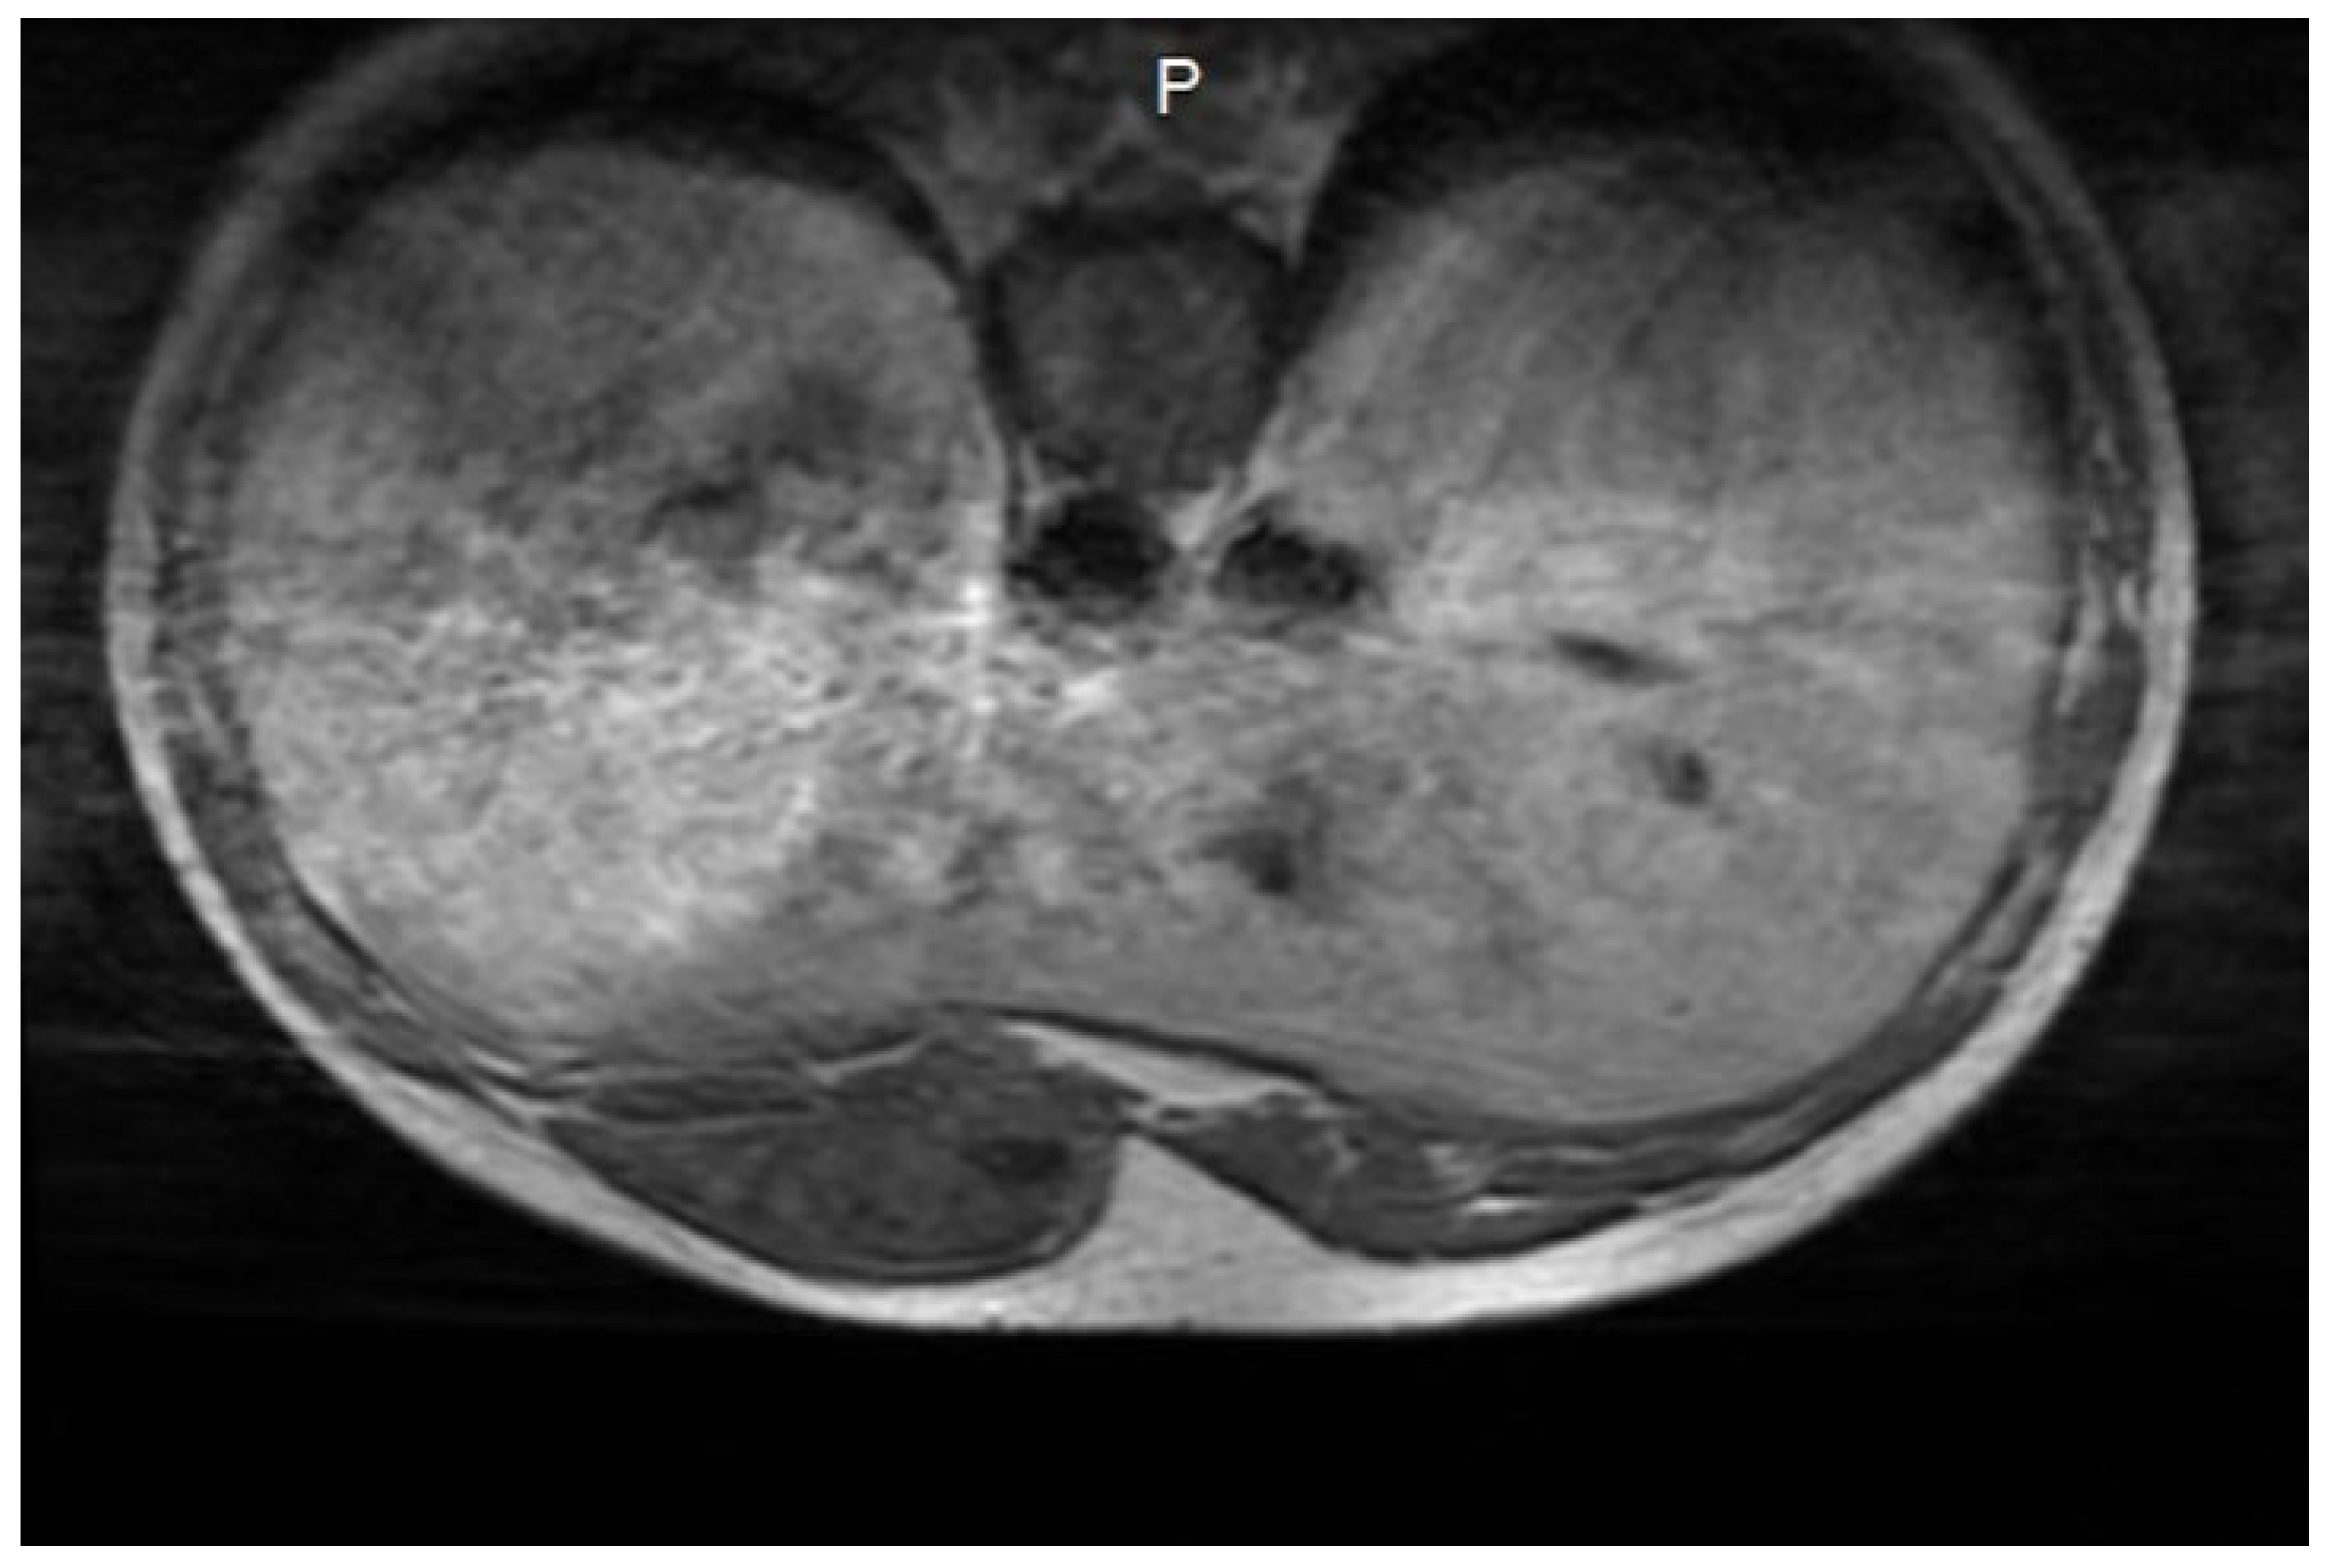

3.1. Diagnosis and Imaging Characteristics